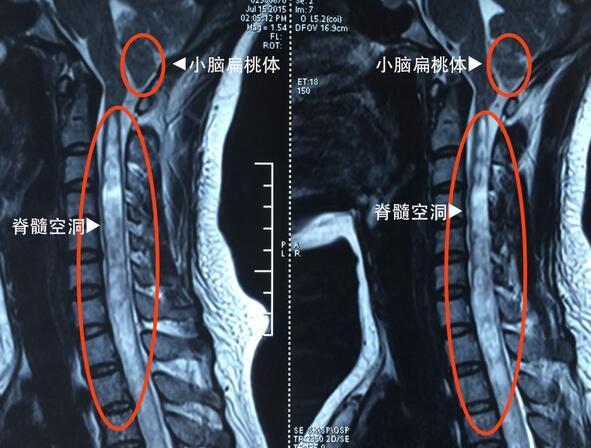

脊髓空洞癥就是脊髓的一種慢性、進(jìn)行性的病變。病因不十分清楚,其病變特點(diǎn)是脊髓(主要是灰質(zhì))內(nèi)形成管狀空腔以及膠質(zhì)(非神經(jīng)細(xì)胞)增生。常好發(fā)于頸部脊髓。那么脊髓空洞到底有哪些癥狀呢?

脊髓空洞癥是各種原因引起的脊髓內(nèi)空洞形成,會(huì)使患者出現(xiàn)一系列臨床癥狀,主要表現(xiàn)有三大癥狀,是肢體感覺障礙,第二是肌肉萎縮,第三是運(yùn)動(dòng)障礙。

脊髓空洞癥由于脊髓比較長(zhǎng),所以不是每一個(gè)部位都出現(xiàn)癥狀,關(guān)鍵是看脊髓的空洞發(fā)生在哪一段。比如如果發(fā)生在頸段時(shí),主要表現(xiàn)是上肢肌肉的萎縮或者感覺的障礙,或者是運(yùn)動(dòng)的障礙。